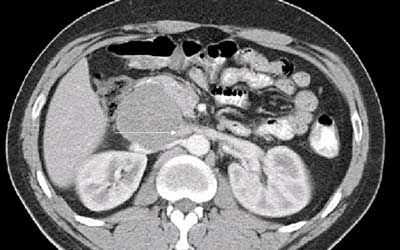

При осмотре в брюшной полости пальпируется подвижное безболезненное и относительно плотное образование. Данные лабораторных анализов — без отклонений, опухолевые маркеры в пределах нормы. Рентгенография брюшной полости показала нормальное распределение газов в кишечнике. Ультразвуковое исследование выявило анэхогенное кистозное образование, занимающее полностью переднюю и правую часть брюшной полости. Каких‑либо патологических изменений кишечника, а также свободной и локализованной жидкости в брюшной полости не обнаружено. КТ брюшной полости и МРТ выявили образование больших размеров — 35×20×10 см, располагавшееся в брюшной полости и полости малого таза, не связанное с какими‑либо органами (рисунок 1).

Обзорная рентгенограмма и контрастная рентгенография с барием часто дают нормальные результаты или показывают наличие какого‑то образования, смещающего кишечник [6, 9]. УЗИ брюшной полости, КТ и МРТ более информативны [7, 10]. Они могут показать кистозный характер образования, его размеры, расположение и связь с прилежащими органами, а также характер содержимого и стенок кисты [2, 6].

При УЗИ кисте брюшной полости выглядит как анэхогенное образование с акустическим усилением [6, 7, 9]. КТ и МРТ выявляют образование, наполненное жидкостью, с сигналом слабой интенсивности на Т-взвешенных изображениях, без различимых стенок и внутренних перегородок [7, 9]. Данные лабораторных исследований — неспецифичны. Обычно дополнительные диагностические мероприятия (тонкоигольная аспирационная биопсия с цитологическим анализом или обзорная лапароскопия) не проводятся [2].